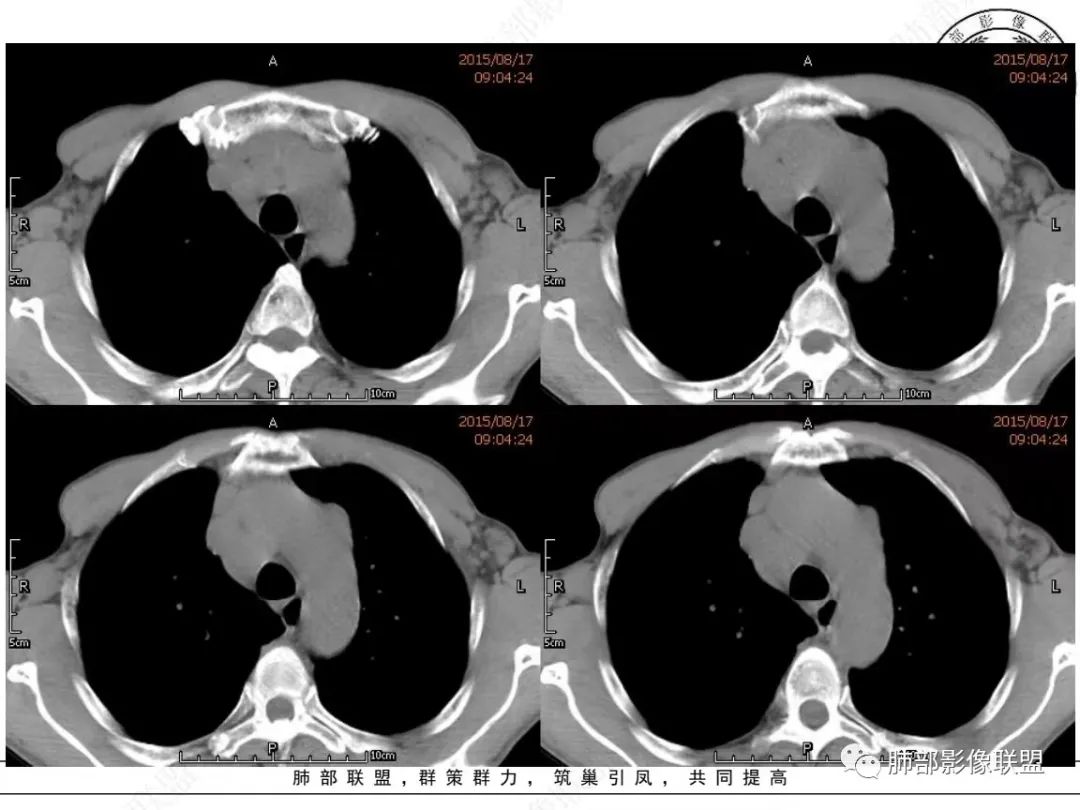

宇宙:右肺下叶小结节,右肺门及中后纵膈淋巴结肿大融合,强化均匀,主支气管、中间段及下叶支气管受压变窄,右下肺静脉受压变窄,考虑小细胞癌,鉴别淋巴瘤

丽:老年男性,纵隔及肺门多发肿大淋巴结,相互融合呈团块状,包绕支气管官腔,呈针尖样狭窄,增强后轻度强化,考虑小细胞肺癌

放射线:纵隔及肺门淋巴结肿大相互融合呈冰冻纵膈,支气管受压变窄呈针孔样,老年男性吸烟患者,考虑小细胞肺癌。

我只是邓较瘦:晨读老年男性,长期吸烟。右肺门、纵隔多发肿大淋巴结、融合成团块,中间支气管、右肺下叶支气管受压变窄,增强扫描强化程度较轻,血管包埋。另两侧腋窝亦见多发肿大淋巴结。常规恶性没问题,小细胞?淋巴瘤?但是於老师的病例总感觉没那么简单。

谢加平:纵隔内中后纵隔及右肺门淋巴结肿大,形成大肿块,整体密度均匀,并轻度强化,见“血管飘浮”征,包绕气管分叉及右主支气管及中间段支气管明显受压狭窄,并包埋右肺门血管束,无侵蚀破坏,右肺动脉后壁见压迹影,右肺下叶背段有阻塞性炎症,首选淋巴瘤,支气管超声内镜活检,明确诊断!

理由:四点,1、整个病灶位于纵隔中央后主,且以后纵隔为主,2、病灶内血管漂浮,3、肺内无原发灶,没找到“娘”。4、颌下淋巴结穿刺未找到小细胞癌。所以肯定先考虑淋巴瘤。